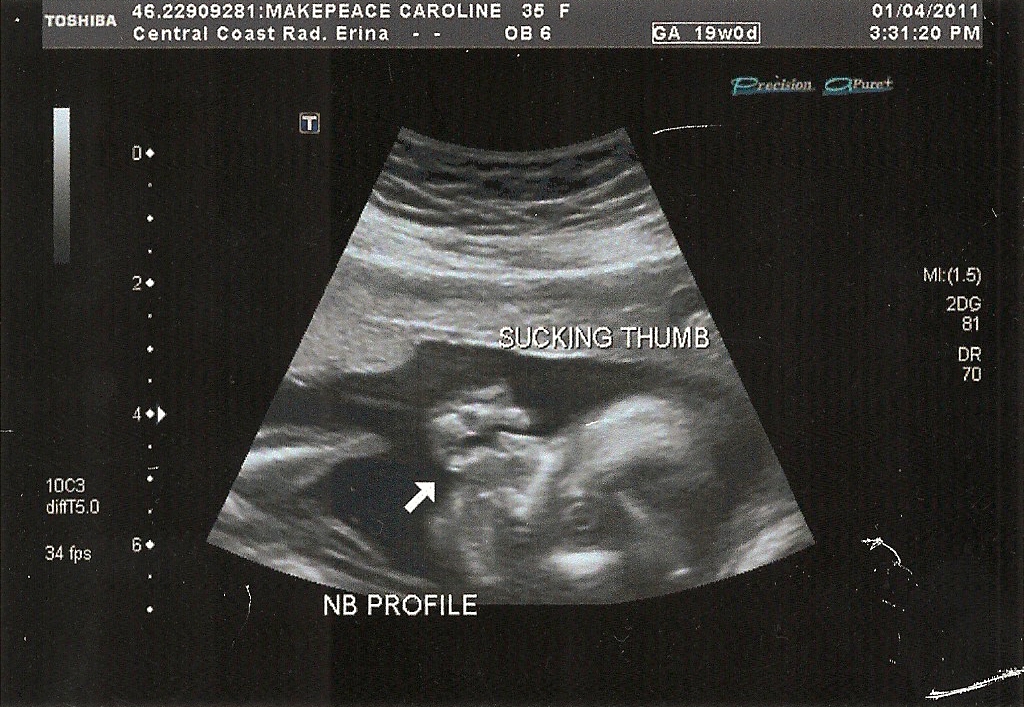

Now I have time to bond and prepare and focus on all the wonderful things about having another girl. I know the most important thing is that she is healthy and I am so grateful for that. And when I look at the photo of her sweet little face sucking her thumb, I am already filled with love for her.